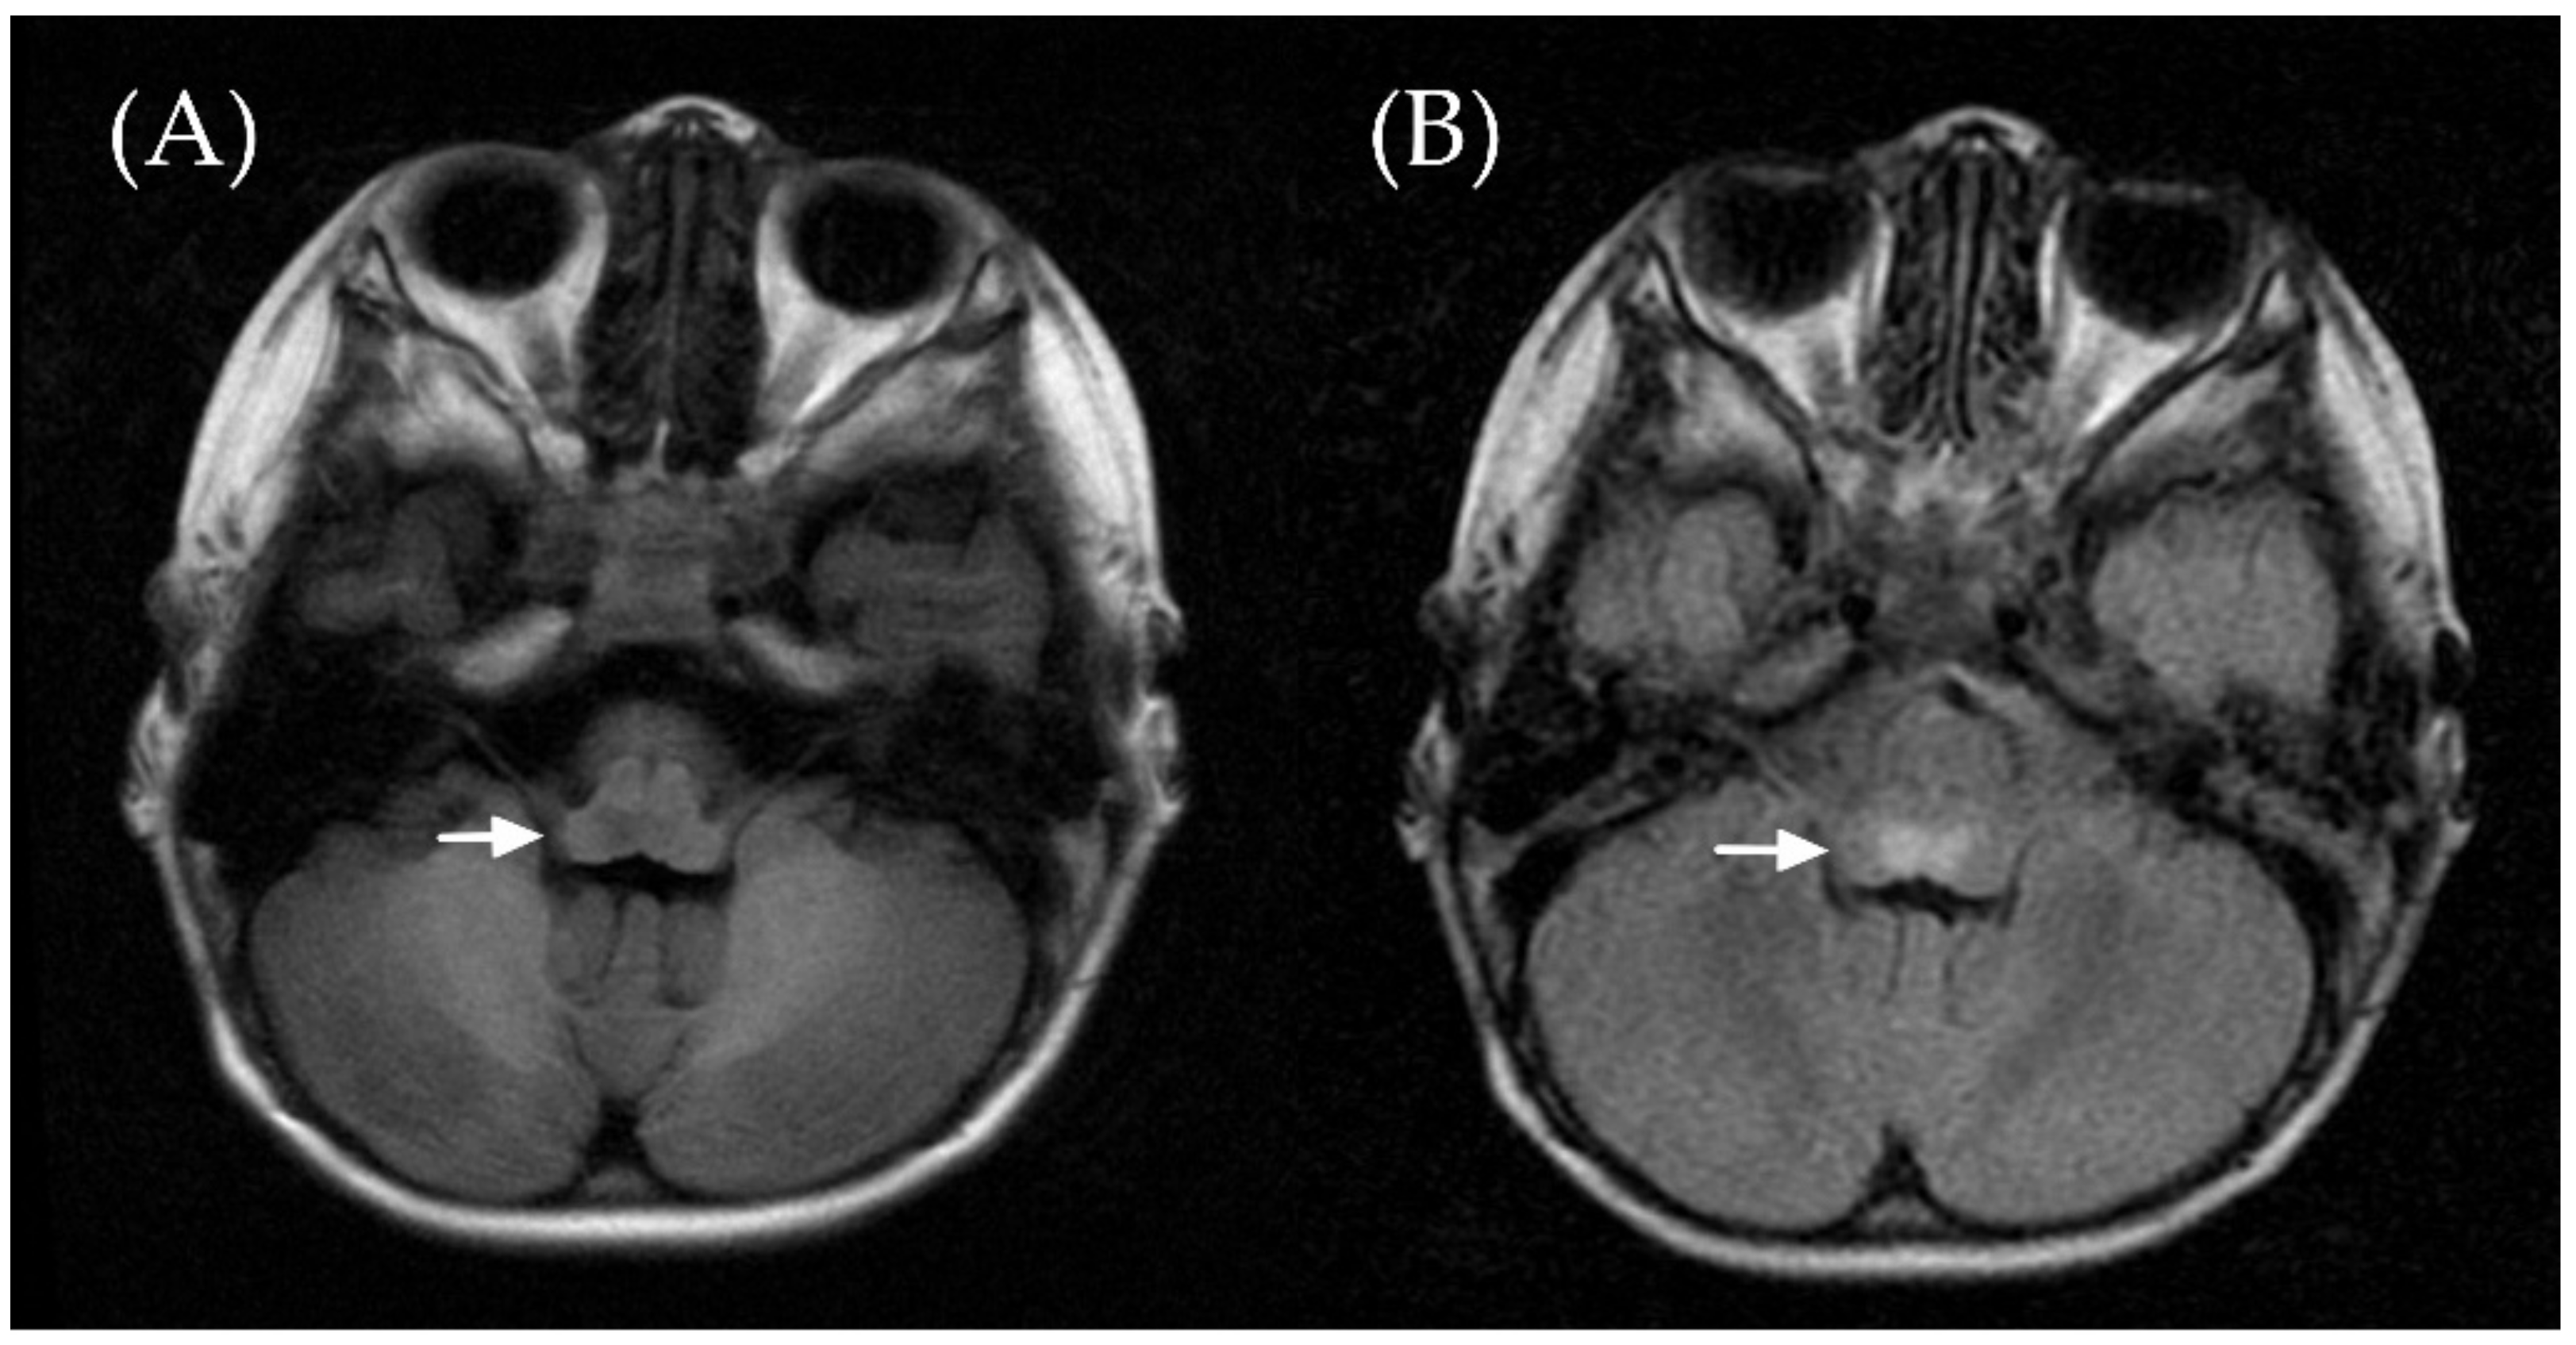

2. Case Report